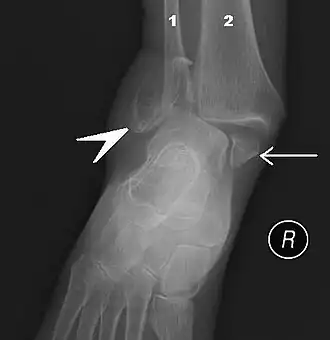

![]() Правый голеностопный сустав, вид сбоку. | |

В ходе объективного обследования применяются физикальные методы исследования: осмотр, пальпация. Немаловажное значение имеет тщательный сбор анамнеза. Из инструментальных методов большое распространение получило рентгенологическое исследование голеностопного сустава в прямой, боковой, а также косой проекции. В настоящее время для диагностики применяют также артроскопию.

Правый голеностопный сустав, снаружи.

Правый голеностопный сустав.- Схема правого голеностопного сустава.